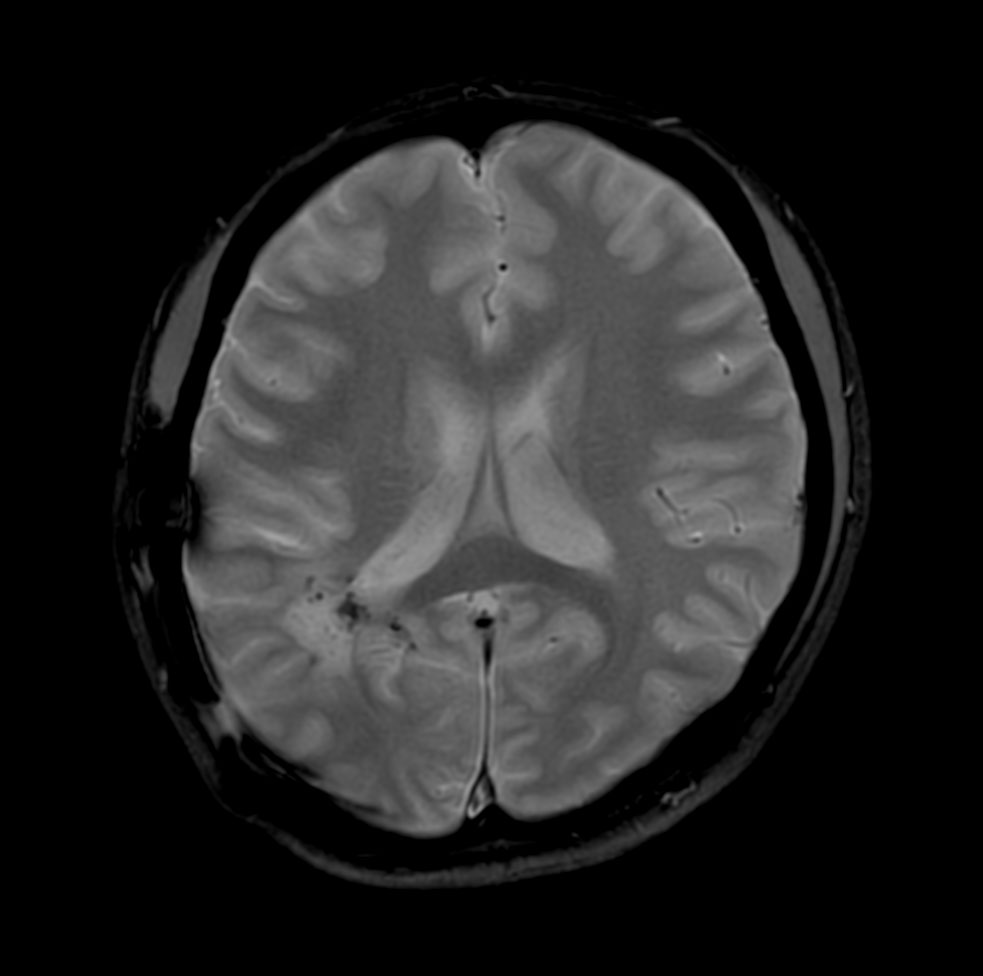

Axial DWI (b1200)